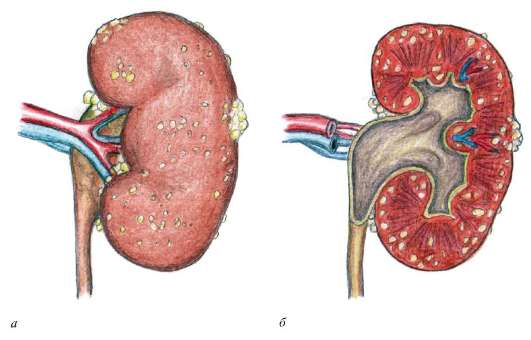

Понимание кавернозного туберкулеза почки